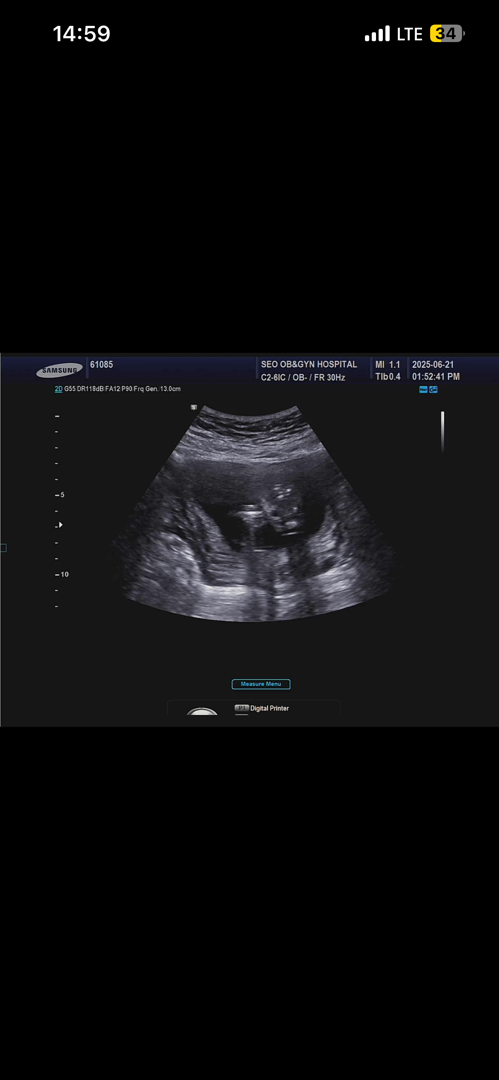

15주 4일 다리사이 봐쥬세영 ㅠㅠ

선생님은 확실하지 않다고 하시는데 이정도면 딸로 봐도될까요??